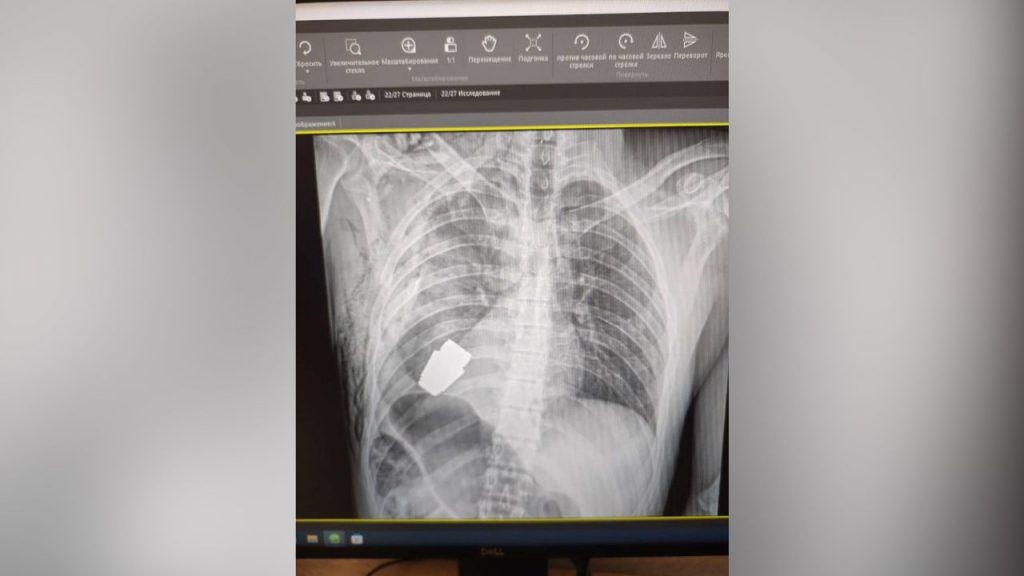

Οι φωτογραφίες που κοινοποιήθηκαν στη σελίδα της Ουκρανικής Στρατιωτικής Ιατρικής στο Facebook τη Δευτέρα περιελάμβαναν μια ακτινογραφία του άνω μέρους του σώματος του στρατιώτη με ορατή τη χειροβομβίδα, σύμφωνα με το CNN.

Η χειροβομβίδα ήταν τύπου VOG, ένα μοντέλο που συνήθως χρησιμοποιείται σε εκτοξευτές χειροβομβίδων.